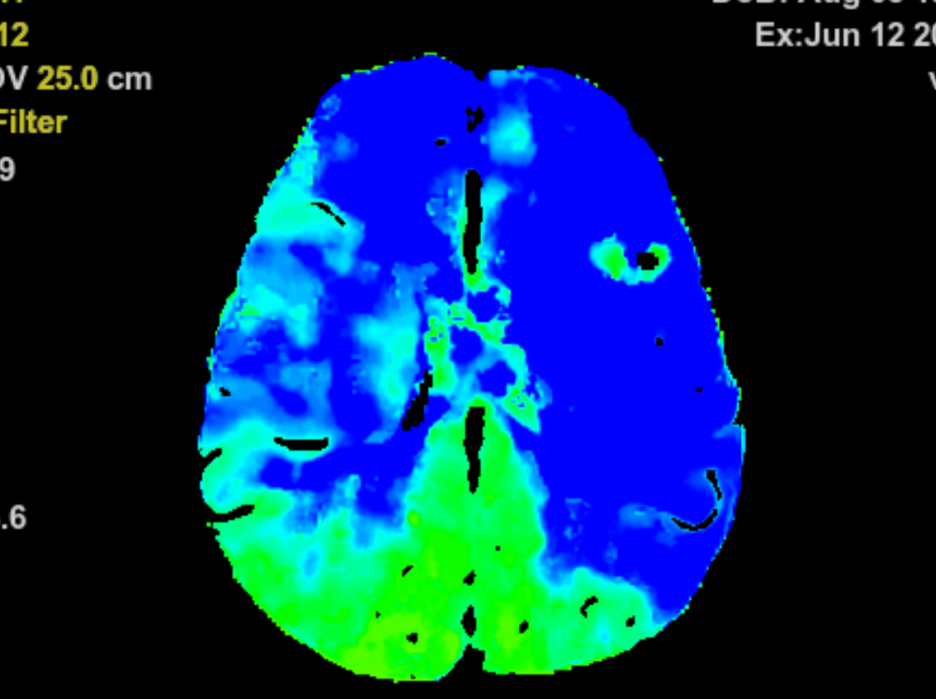

2小时后,新的供血通路成功建立。术后脑血流灌注成像图显示,此前的缺血区域供血基本恢复了正常。患者也表示,眼睛看东西清晰了很多,表明手术疗效初步显现。

术后脑血流灌注成像图显示,黄色和红色区域基本消失,大脑供血恢复明显